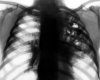

Чаще всего воспаление плевры (плеврит) не является какой-либо отдельной болезнью, а скорее возникает как симптом осложнения при каком-либо другом заболевании легких или дыхательных путей. Плеврит бывает экссудативный, при котором происходит накопление жидкости и уменьшается ее отток из плевральной полости, а также сухой, который проявляется образование налета на стенках плевры.

Плевриты вызываются либо инфекционными заболеваниями (вирусами, бактериями или грибком) или же неинфекционными системными заболеваниями - ревматоидным артритом, красной волчанкой и другими.

Проявляется болезнь сильной болью в боку, которая время от времени усиливается, а при экссудативном плеврите боль сопровождается сильным кашлем.

Лечение плевритов проводят в зависимости от причины, вызвавшей болезнь - назначаются антибиотики, противовоспалительные или же противотуберкулезные препараты, а также различные болеутоляющие средства. При накапливающейся в плевральной полости жидкости иногда прибегают к плевральной пункции.